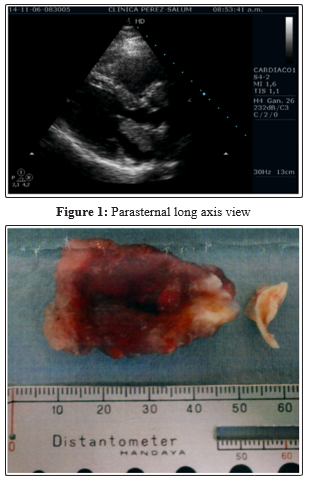

She came to my laboratory by November 6th 2014 just to do those studies. In the vascular Doppler of Carotid and Vertebral arteries no significant lesions were reported. In the echocardiography it was possible to see a mass in left atrium with gelatinous aspect with approximately 4.2 cm by 2,5 cm. It seemed to had a base of implantation in the atrial septum and it was mobile.

The possible diagnosis was a left atrial myxoma. For this reason, referral to a cardiac surgeon is asked. She went to the Division of Cardiovascular Surgery of Jichi Medical University (Japan). There she was submitted to surgery in 19th November 2014, without complications; and the diagnose was confirmed. From this day until nowadays, she is assympthomatic.

Figure 2: surgical specimen (courtesy of Prof. Hirotaka Sato, Division of Cardiovascular Surgery of Jichi Medical University, Japan)